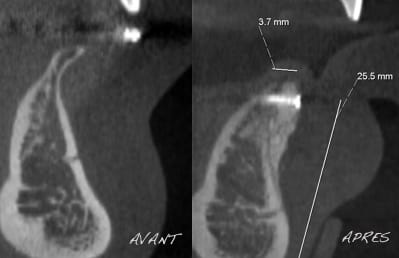

Pour l'anamnèse, le patient présentait plusieurs aplasies au niveau du bloc incisif inférieur.

Pour les coupes tomo, voici avant/après au niveau du site 41-42.